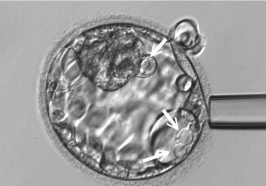

![]() 无液泡 |

![]() 有液泡 |

在826名患者的3351个囊胚中,发现903个具有液泡,占总数的26.9%。透过胚胎着床前染色体筛检(PGT-A)数据分析,发现带有液泡的囊胚具有染色体整倍体的比例显著低于无液泡囊胚(28.8% vs. 35.5%;p <0.001),且胚胎质量也显著较差(30.6% vs. 18.2%,p <0.001)。逻辑回归分析显示,整倍体囊胚的发生与无液泡、母体年龄和良好胚胎质量呈正相关(无液泡组: 调整后OR = 1.291, 95% CI = 1.089-1.530; 年龄 < 38 岁: 调整后OR= 1.989, 95% CI = 1.692-2.337; 良好胚胎质量: 调整后OR = 1.703, 95% CI = 1.405-2.064)。移植单一具有液泡的整倍体囊胚后,其着床率和活产率显著比较无液泡的囊胚低(35.5% vs. 56.6%, p = 0.033; 29.0% vs. 52.2%, p = 0.020)。无液泡的囊胚与植入最终活产率呈正相关(调整OR = 2.792,95% CI = 1.180-6.608)。